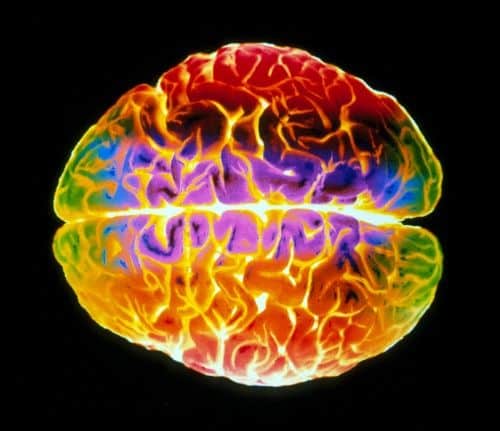

Empathie ist ein wichtiger Mechanismus im sozialen Miteinander. Sie trägt dazu bei, dass wir anderen Menschen nicht nur aus eigennützigen Motiven helfen, etwa, um als Revanche etwas von ihnen fordern zu können: Durch das Nachempfinden des Zustands einer anderen Person fühlen wir uns in sie ein und können sie besser so behandeln,

Wie wir echtes Leid von simuliertem Schmerz unterscheiden